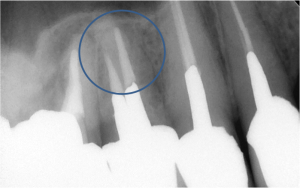

続いての症例です。

これもまた非常に珍しい症例です。

下顎第一大臼歯ですが、近心根(レントゲンではこの歯の右側の根)はたいてい2根管

まれに1根管です。

しかし、この根は3根管を有していました。

左のレントゲンでは2根管しか治療されてないのがわかると思います。

しかし、右のレントゲンでは明らかに3根管あることが分かります。

この根の3根管は0.9%と言われています。非常に珍しいです。

すべての根管が治療されてなければ治らないとは限りませんが、非常にレアな症例では、

その見落とされた根管を処置しなければ治らないこともあります。

全てはマイクロスコープで歯の中を覗いたからわかることです。

裸眼では、まず見つけることは不可能に近いです。

いやー、マイクロスコープってすごいですね。